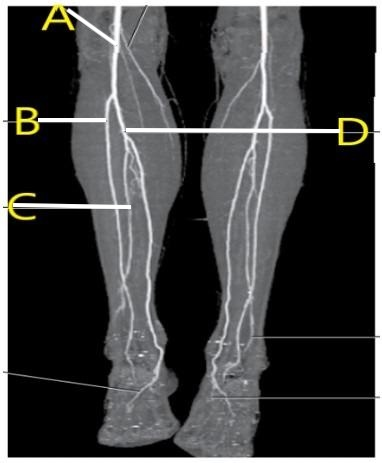

Which letter is the popliteal artery?

A

left popliteal artery